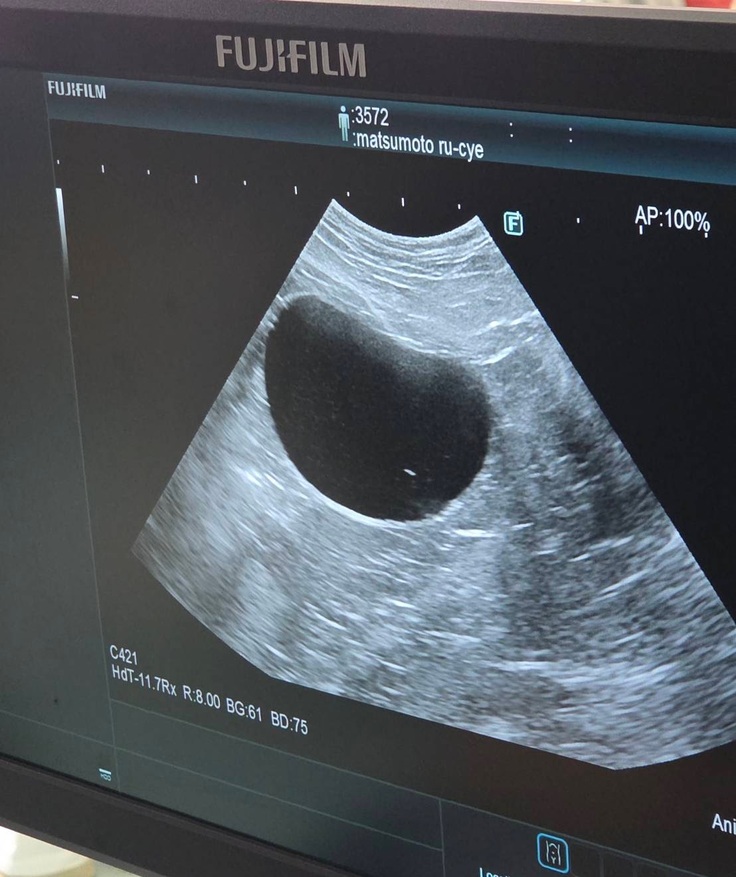

血液検査の写真は撮れなかったのですが、エコー検査では

↓膀胱転移なし